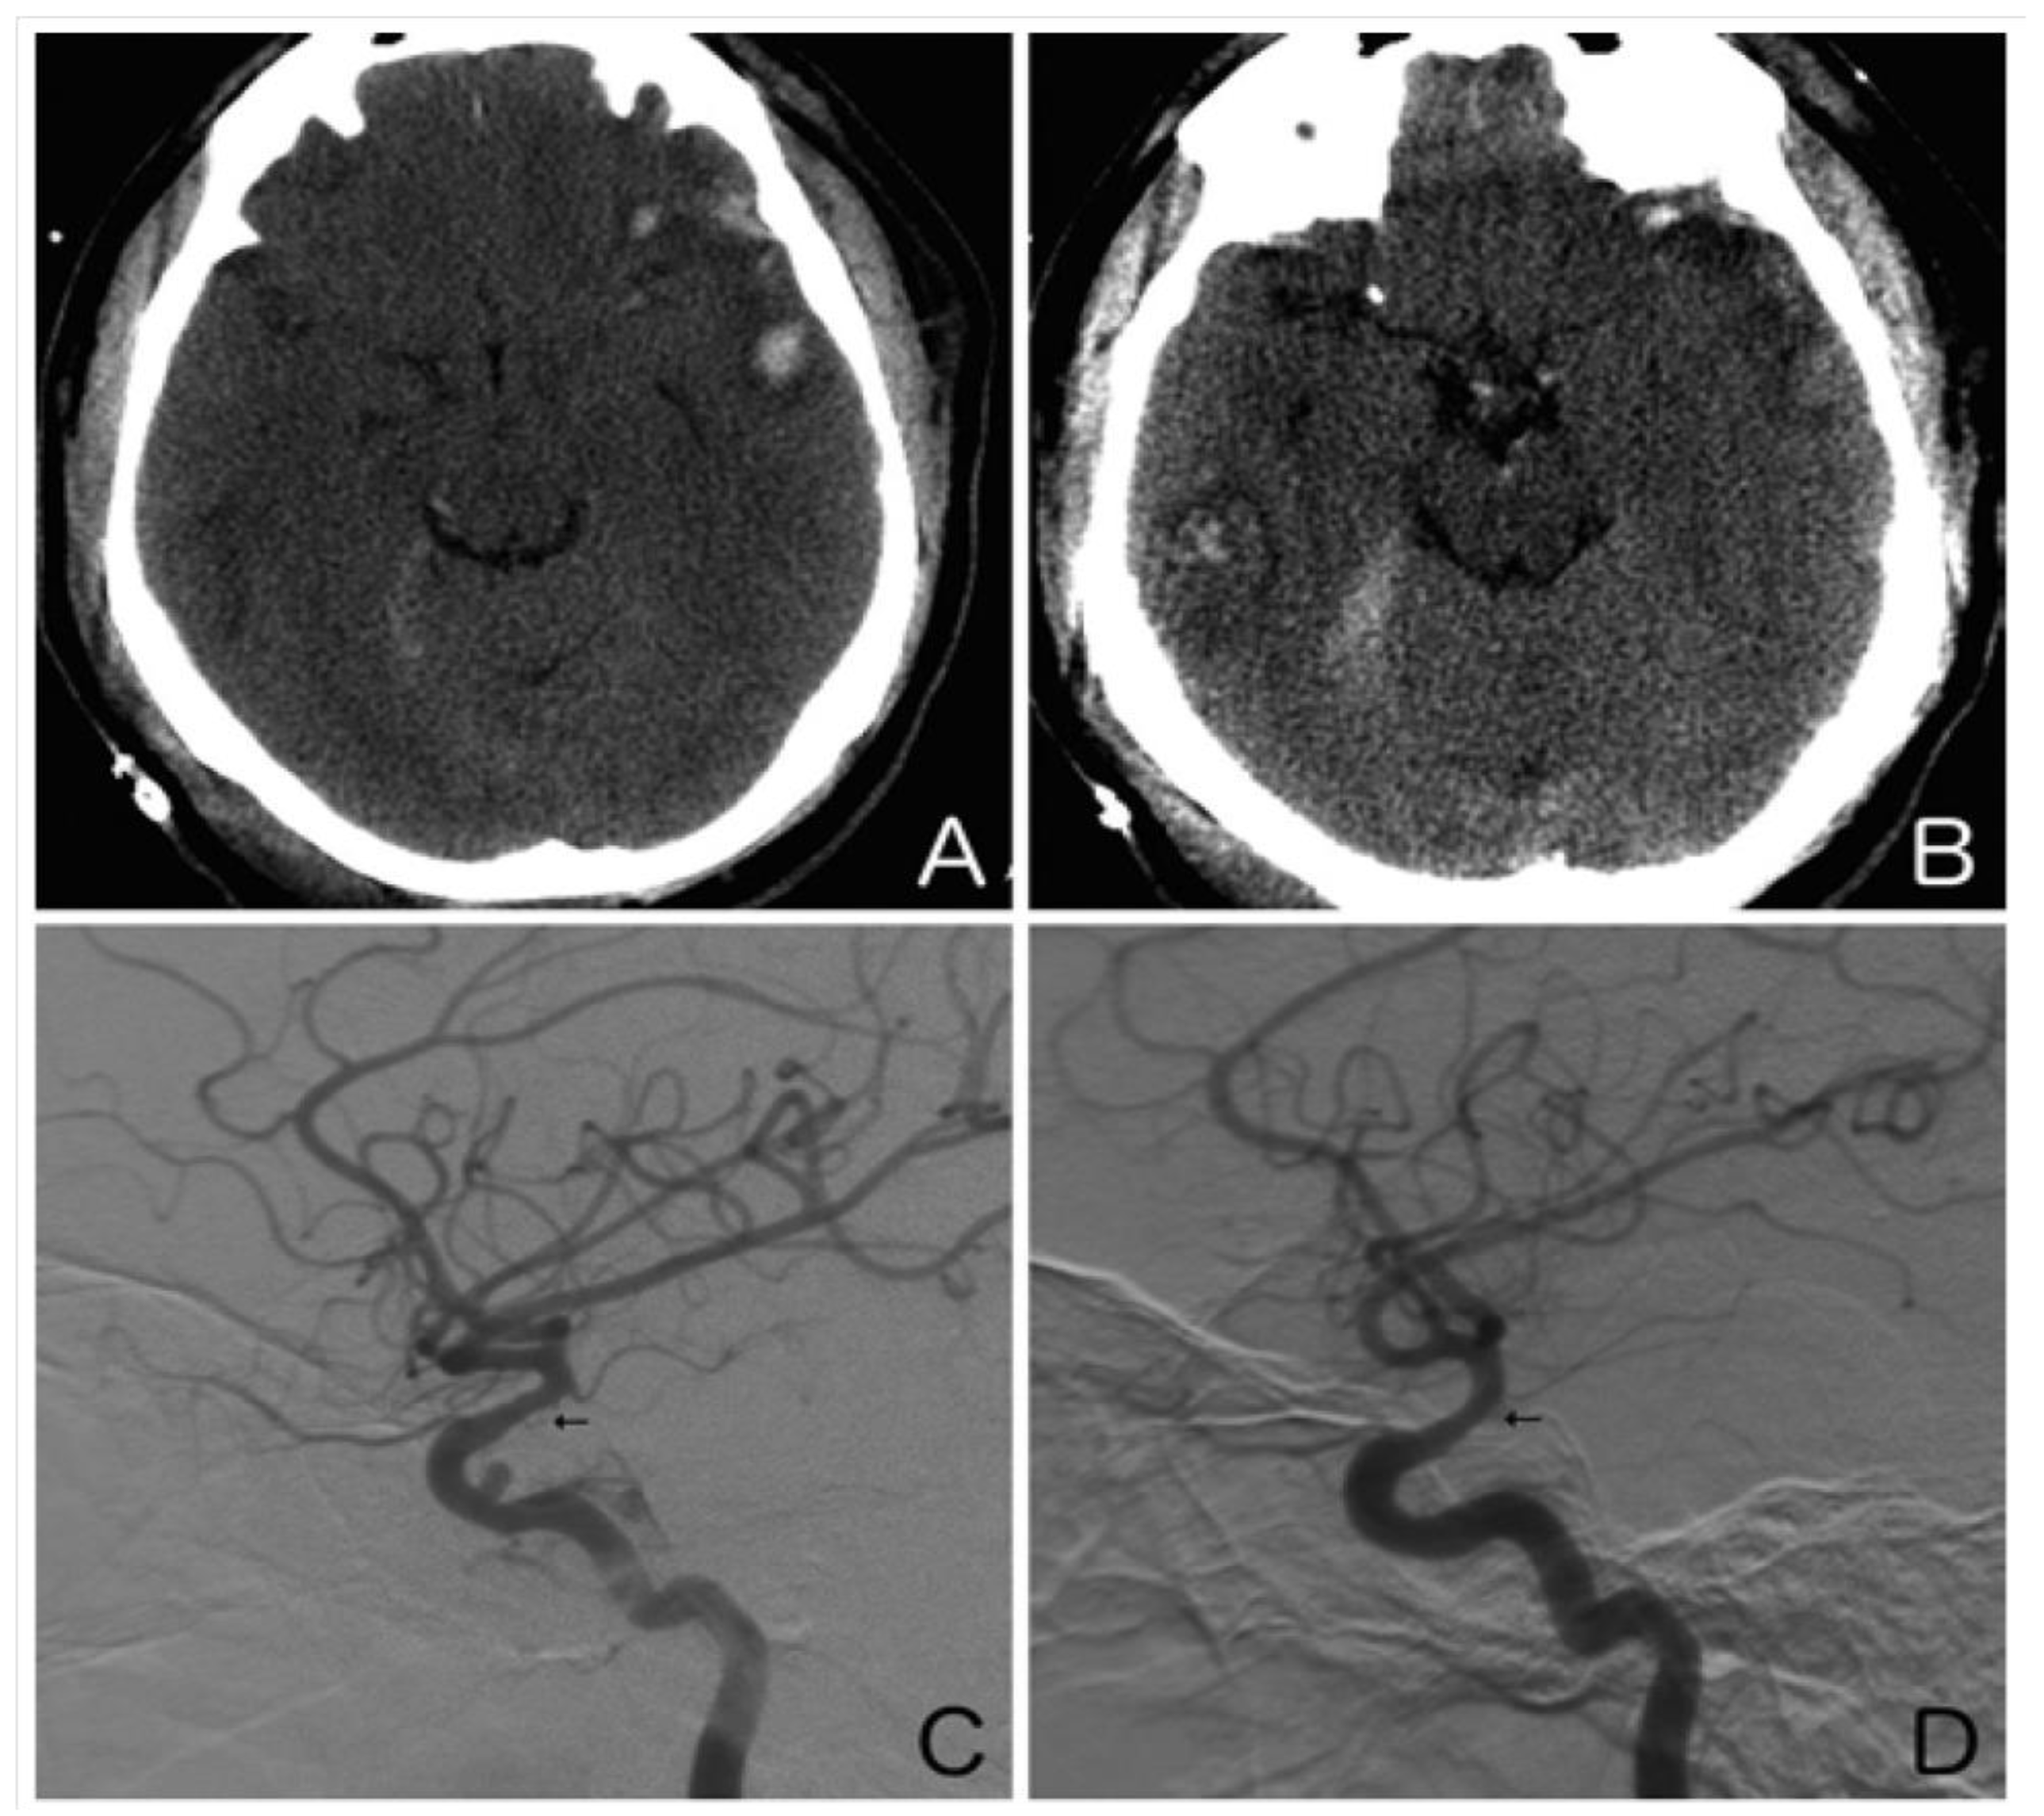

3.1. Grade I–II: Dissection

3.2. Grade III: Pseudoaneurysm

5. Post-Traumatic Vasospasm